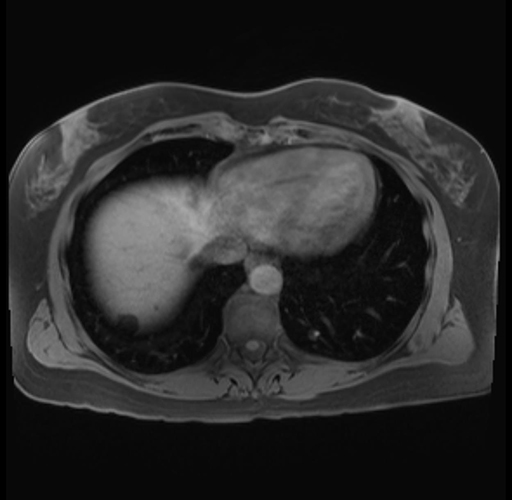

Imaging Analysis

Look through the patient's CT scan to identify any areas of concern for the necessary procedure.

Based on your CT findings, which issue(s) are present and would give reason for "planned slowing down moment(s)" in this case?

Considering a standard distal pancreatectomy procedure, what step(s) of the operation would you do differently in this case?